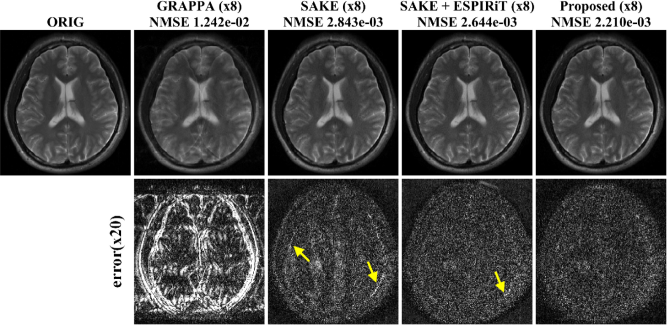

Next we compared our parallel imaging results with those of the existing approaches for additional multichannel brain data set. The NMSE results in Fig. 4 showed that ALOHA was most accurate. From the difference images at the second row of Fig. 4, we observed that proposed method provided reconstruction results more accurately than other algorithms. In SAKE, the structures were distorted around the inner skull and the boundaries of tissues. In SAKE with ESPIRiT, overall reconstruction errors were higher than those from ALOHA and there were still remaining errors around the skull. The reconstruction time was 22.2sec with our preliminary GPU implementation of ALOHA, which attained a speed-up factor of 5 compared to CPU implementation. On the other hand, the computational time for MATLAB version of GRAPPA, SAKE, and SAKE+ESPIRiT were 9s, 320.4s, and 21.6s, respectively.